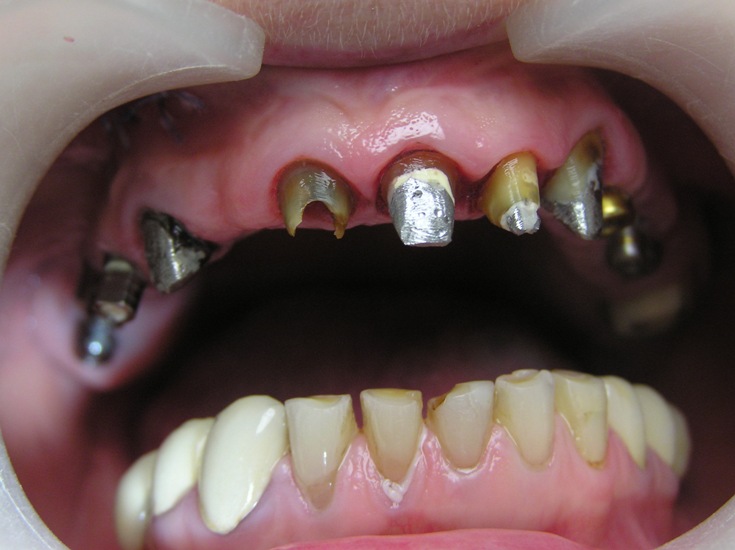

Clinical case: Patient T, 55 years old.

Diagnosis: Combined Maxillary Dentition Defect (Ye. I. Gavrilov).

Treatment: Implantation in the area of 14, 15, 16, 17, 24, 25 and 26 teeth with Alpha Dent Implants.

Fixation of temporary bridge prosthesis, making of metal-ceramic bridge prosthesis.